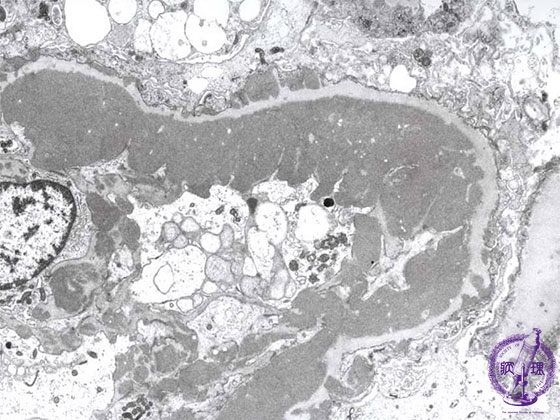

- (6)Lupus Glomerulonephritis

Microscopic findings (electron microscopy): There are electron dense subendothelial deposits (yellow dotted line) which correspond to the wire-loop lesion.